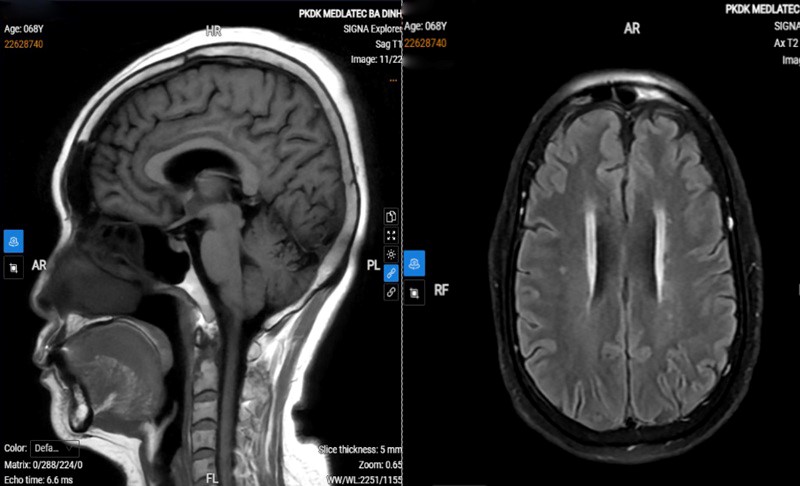

| Tổn thương của bệnh nhân. |

Kết quả chụp cộng hưởng từ (MRI) cho thấy dấu hiệu thoái hóa myelin chất trắng; đo lưu huyết não ghi nhận giảm lưu lượng hệ động mạch đốt sống, thân nền bên trái. Một số chỉ số khác như điện tim, siêu âm tim trong giới hạn bình thường, nhưng xét nghiệm máu phát hiện đường huyết và mỡ máu tăng.

Từ các kết quả này, bệnh nhân được chẩn đoán đau thần kinh chẩm lớn bên trái trên nền tăng huyết áp, rối loạn chuyển hóa lipid và tiền đái tháo đường. Bệnh nhân được điều trị bằng phương pháp tiêm phong bế thần kinh chẩm, kết hợp dùng thuốc và hướng dẫn tập vật lý trị liệu tại nhà.